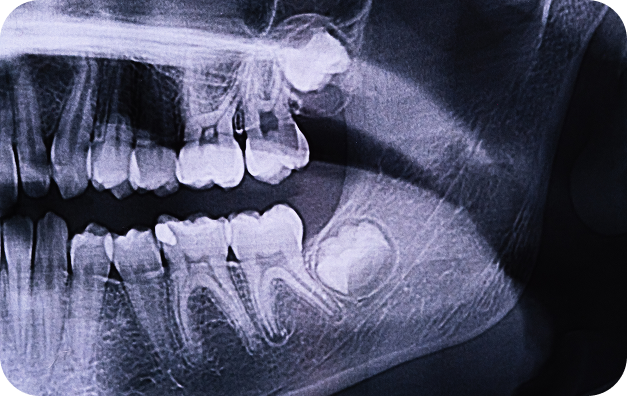

Cirugía Maxilofacial

Cirujano Maxilofacial en CDMX

En Hospital Polar San José, ofrecemos atención especializada en cirugía maxilofacial, con el objetivo de mejorar tanto la función como la estética de tu rostro y mandíbula. Nuestro equipo de cirujanos maxilofaciales, con años de experiencia, está comprometido a brindarte un enfoque integral y personalizado, asegurando que cada uno de tus tratamientos o procedimientos se realice con el mayor cuidado y profesionalismo.

La cirugía maxilofacial trata problemas como fracturas faciales, malformaciones mandibulares, trastornos de la articulación temporomandibular (ATM), cirugía de encías, implantes dentales, y afecciones como la apnea del sueño o los tumores faciales.

Los procedimientos incluyen cirugías reconstructivas de la mandíbula, corrección de malformaciones, cirugía ortognática (para corregir la posición de los huesos faciales y la mordida), y cirugía de implantes dentales, entre otros.